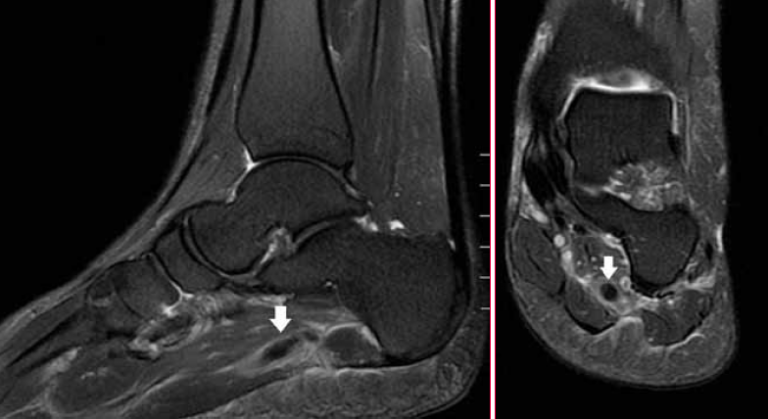

IRM, coupes sagittale (a) et frontale (b) en T2 FatSat. Image en hyposignal tubulaire correspondant à une thrombose du réseau veineux plantaire latéral.